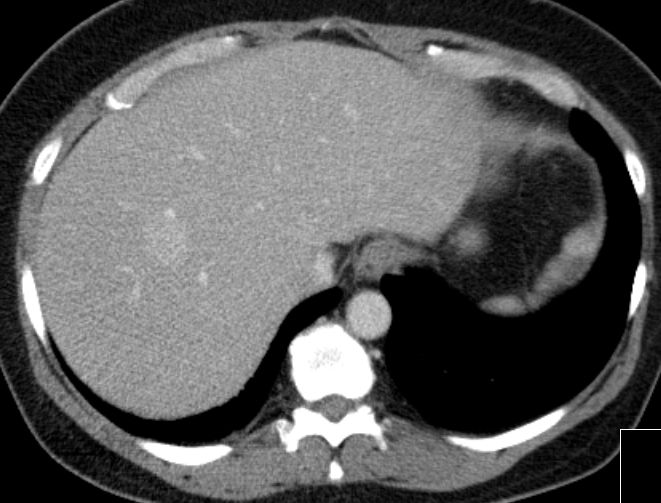

6 Monate später Lebermetastasen.![]() |